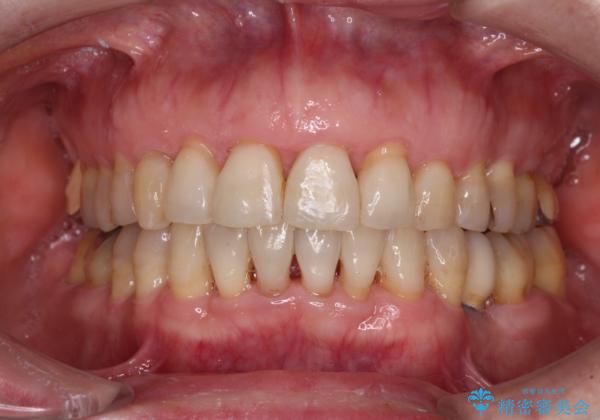

口元の出っ張りとデコボコを改善したい

口元の突出感とデコボコが気になっているとのことでしたが、インプラントが既に3本埋入されていたため、抜歯矯正による口元を引っ込めることができない状況でした。

近医での歯周病治療の影響でブラックトライアングルが発現していたため、IPR(歯と歯の間を削る)で隙間を改善しつつ、インプラントを固定源に歯列全体を後方へ移動させることとしました。